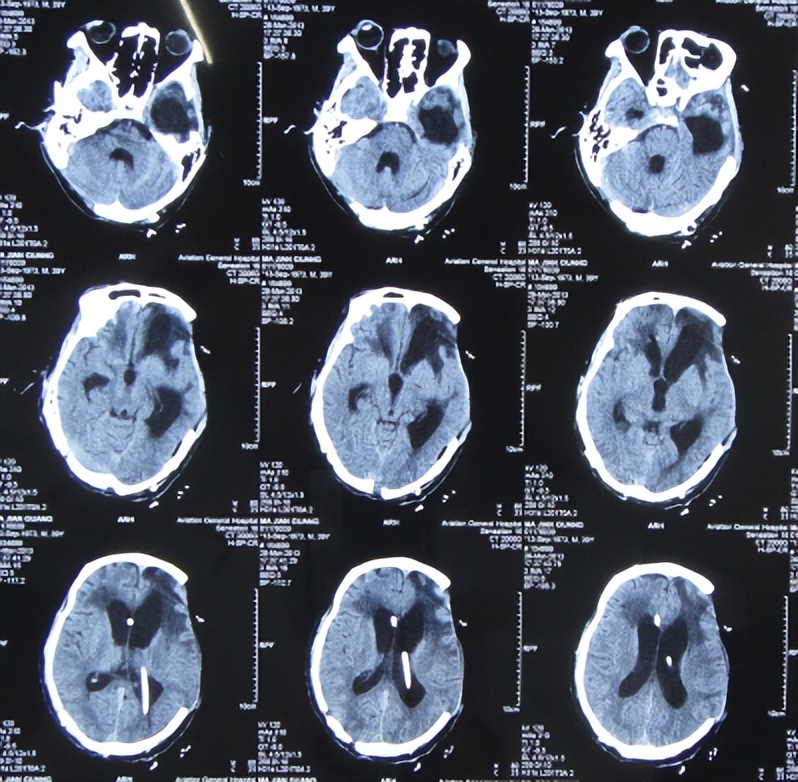

但拔除3天后即2013年1月27日(开颅术后51天),患者意识再次变差昏迷不醒,查头颅CT示,脑积水加重,骨窗组织膨出( 图-8 );右侧肢体肌张力增高、力量减弱,大小便再次*禁失**,继续给予腰大池引流。

图-8: 2013年1月27日头颅CT

腰大池引流术后21天即2013年2月17日(开颅术后72天),查头颅CT示脑室缩小,骨窗变塌陷( 图-9 ),再次拔除腰大池引流管。

图-9: 2013年2月17日头颅CT

但腰大池拔除术后10天即2013年2月27日(开颅术后82天),患者再次意识不清,大小便*禁失**,查头颅CT示脑积水,脑膨出( 图-10 )。

图-10: 2013年2月27日头颅CT

2013年3月5日(开颅术后88天,反复脑积水脑膨出35天)转住入李小勇脑脊液科;入院时:卧床昏迷;刺痛可睁眼、无发音;刺痛左侧肢体可屈曲、右侧肢体肌张力增高;局部颅骨缺损;左额颞顶区骨窗组织膨出、张力较高,左额颞顶区手术切口多处破溃、伴有脓性渗出物;双侧瞳孔对光反射弱,留置鼻饲管;大小便*禁失**( 图-11 )。

入院时查头颅CT示脑积水,左额颞顶及右枕开颅术后、伴局部颅骨缺损,左额颞顶区骨窗脑组织膨出明显、伴片状低密度灶( 图-12 )。

图-12: 2013年3月5日头颅CT